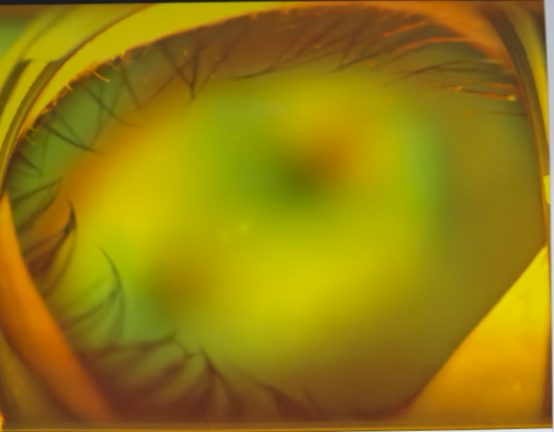

左眼術(shù)前△

左眼術(shù)后△